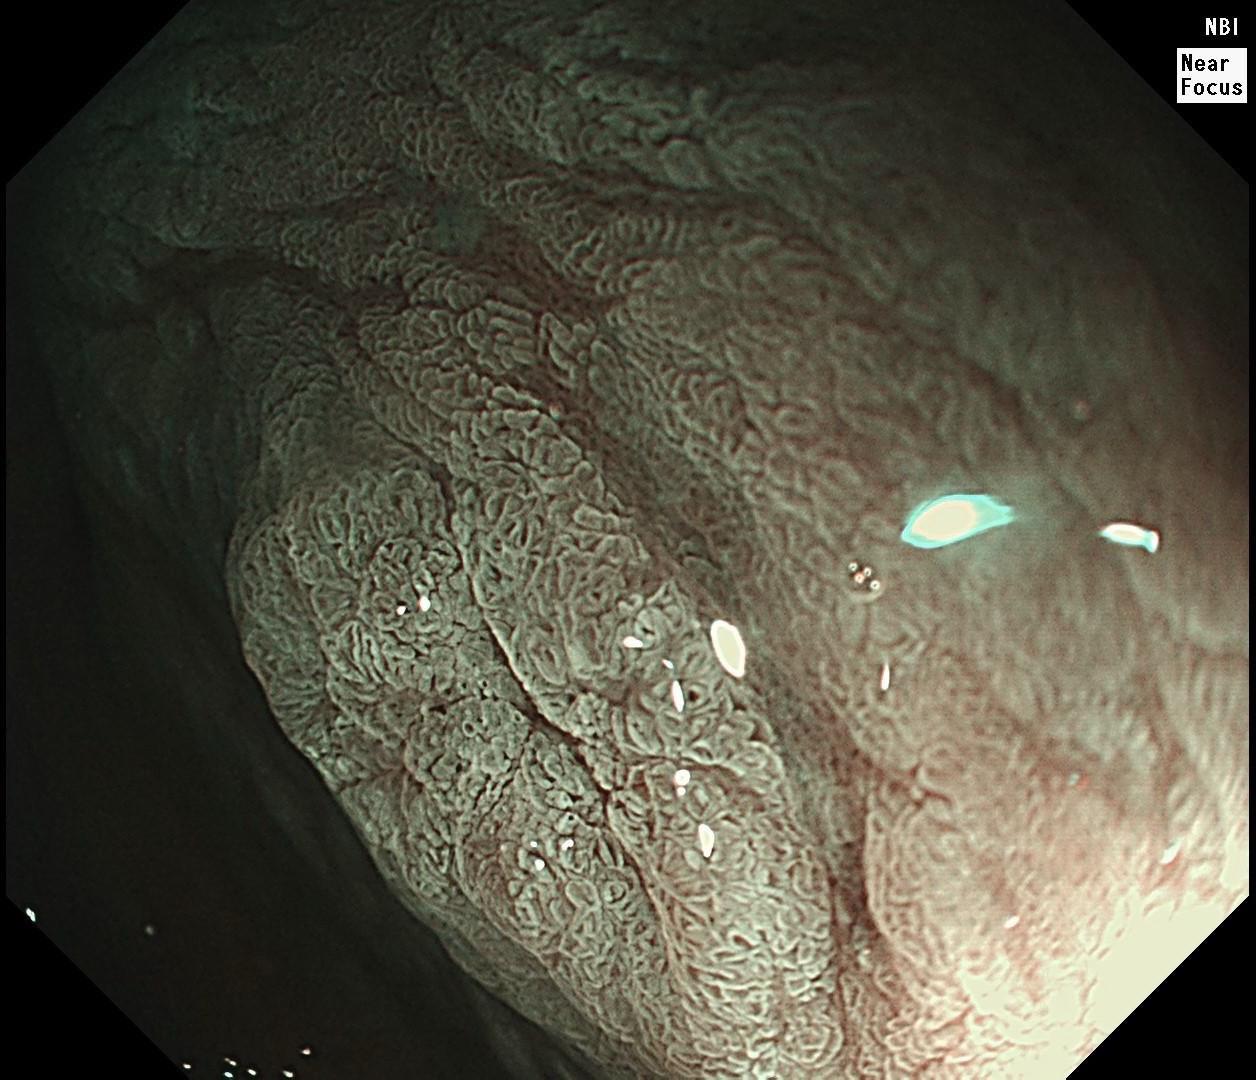

萎缩背景,注意那些微小的发黄色调。